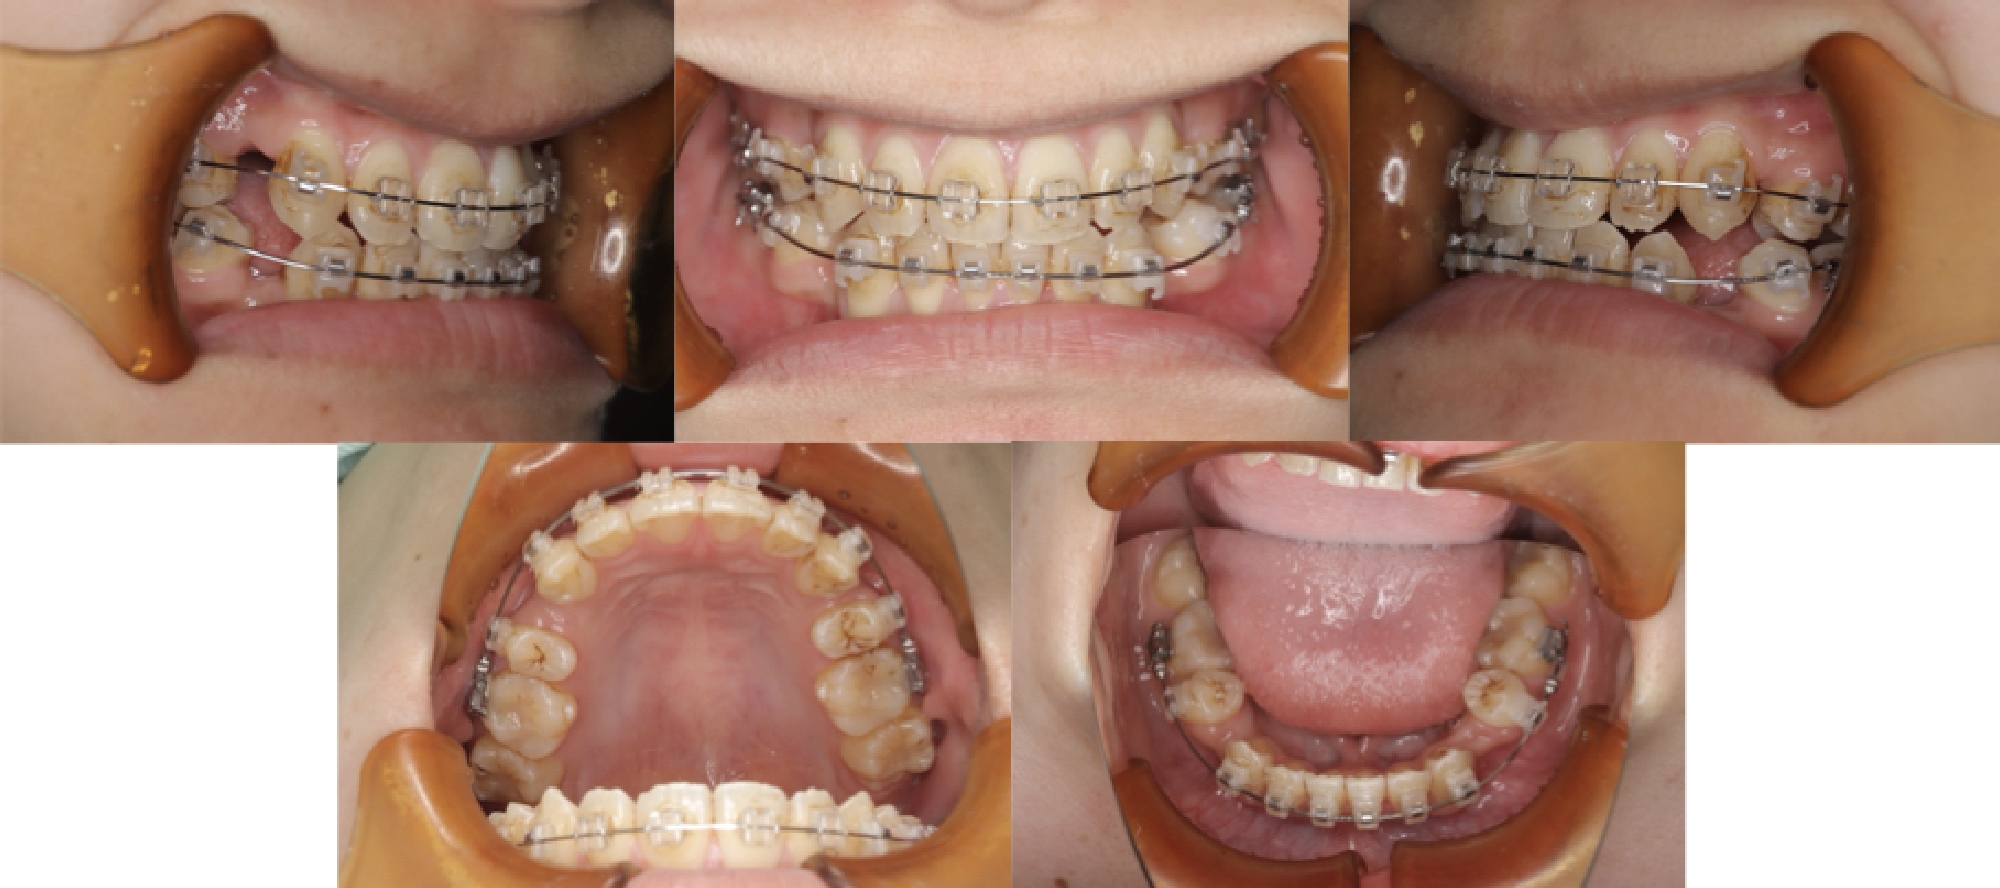

3DCTの治療例

治療中